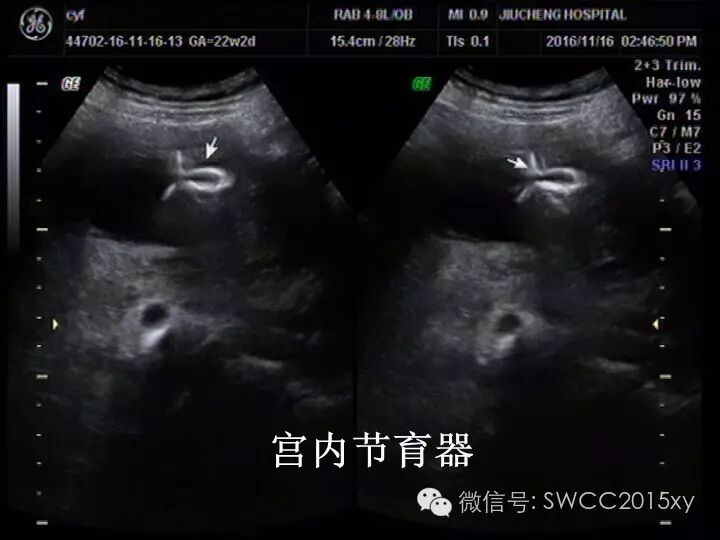

在我们超声的检查中也可以清晰的看到环的位置:下图为T型环和O型环的图片宫内有节育器咋还会怀孕,对胎儿有影响吗?-怀孕期